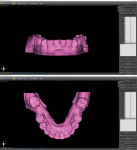

The fabrication of the corticotomy guide was completed by first creating a "generic guide" on the digital model in the planning software. The surgical guide function is typically used for the creation of implant drill guides, but in this case, because no guide tubes were incorporated, the design was just a basic, 3-mm uniform thickness shell that sat over the arch (Figure 3). This provided the foundation for the corticotomy guide. A free 3D modeling application (Meshmixer, Autodesk, Inc.) was then used to create a 15 mm x 15 mm plane measuring 1-mm thick to correspond to the 1-mm width of the piezoelectric surgery tip (Figure 4). After this shape was saved and imported into the planning software, it was duplicated several times and precisely positioned in the surgical guide between the roots of the individual teeth where the corticotomies were to be performed (Figure 5). Because the planes represented the positions where the piezoelectric surgical bone cuts would be made, the plane shapes were checked in all views to ensure that no portion impinged into the tooth roots (Figure 6). Next, the data for the surgical guide and each of the planes were exported and reopened within the 3D modeling application to facilitate a Boolean subtraction. In this manner, the planes were subtracted from the data for the guide, leaving 1-mm slots where the piezo tip could be inserted (Figure 7). Once all of the planes were subtracted, the data was imported back into the planning software to verify the accuracy (Figure 8), and the guide was printed (Objet30 3D printer, Stratasys) (Figure 9).

The optically scanned model of the lower arch was opened in the 3D modeling application to evaluate the integrity of the model, trim off any unnecessary data from the border using the cut tools, and repair any flaws using the analysis repair tool. After the model was corrected and smoothed, the teeth were assessed for degree of rotation, alignment, torqueing, and inclination or retraction. To ensure the correct rotation of the teeth, it is best to create "buttons" on the facial aspects of the canines. This facilitates positive seating and helps predict the planned intrusion of the incisors without resulting in unseating of the aligner. The STL file for the newly refined model was then exported to the planning software for aligner design (Figure 10).

Using the STL file, a new project was started in the planning software's orthodontic module. The positions of the teeth were designated to help the software identify each individual tooth and generate approximate margin tracings. Next, the margins of the teeth were refined, and the software segmented each tooth for individual movement (Figure 11). The teeth were then aligned to their final desired positions, and the rate of movement (ie, weekly, bi-weekly, monthly) was selected (Figure 12 and Figure 13). Using known averages of acceptable tooth movement and sequencing, the software then ran its algorithm and determined the sequential steps of alignment for review. Once approved, the software created individual models for each progressive stage of treatment (Figure 14). After identification labels were digitally embossed onto the models and an orthodontic report for the progressive movement of each tooth was exported and attached to the patient's chart, the STL files for each of the models were ready to be exported for 3D printing.